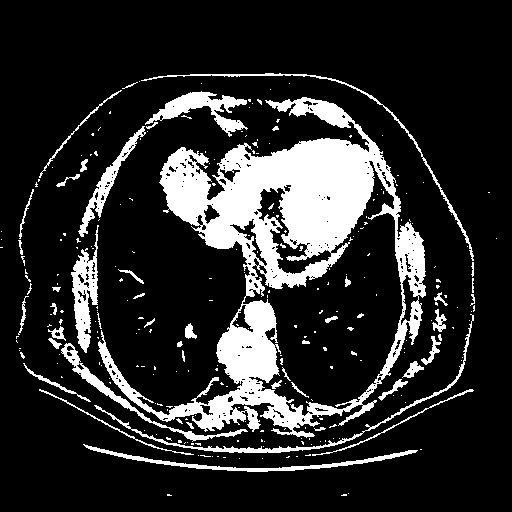

Reconstructed NATIVE CT scan (cycle consistency)

Full window (WL 1023.5, WW 4095 β†’ Low βˆ’1024, High +3071)

Actual HU range: [-1024.0, 3071.0]

Lung window (WL -600, WW 1500 β†’ Low βˆ’1350, High +150)

Actual HU range: [-1350.0, 150.0]

Mediastinum window (WL 40, WW 400 β†’ Low βˆ’160, High +240)

Actual HU range: [-160.0, 240.0]